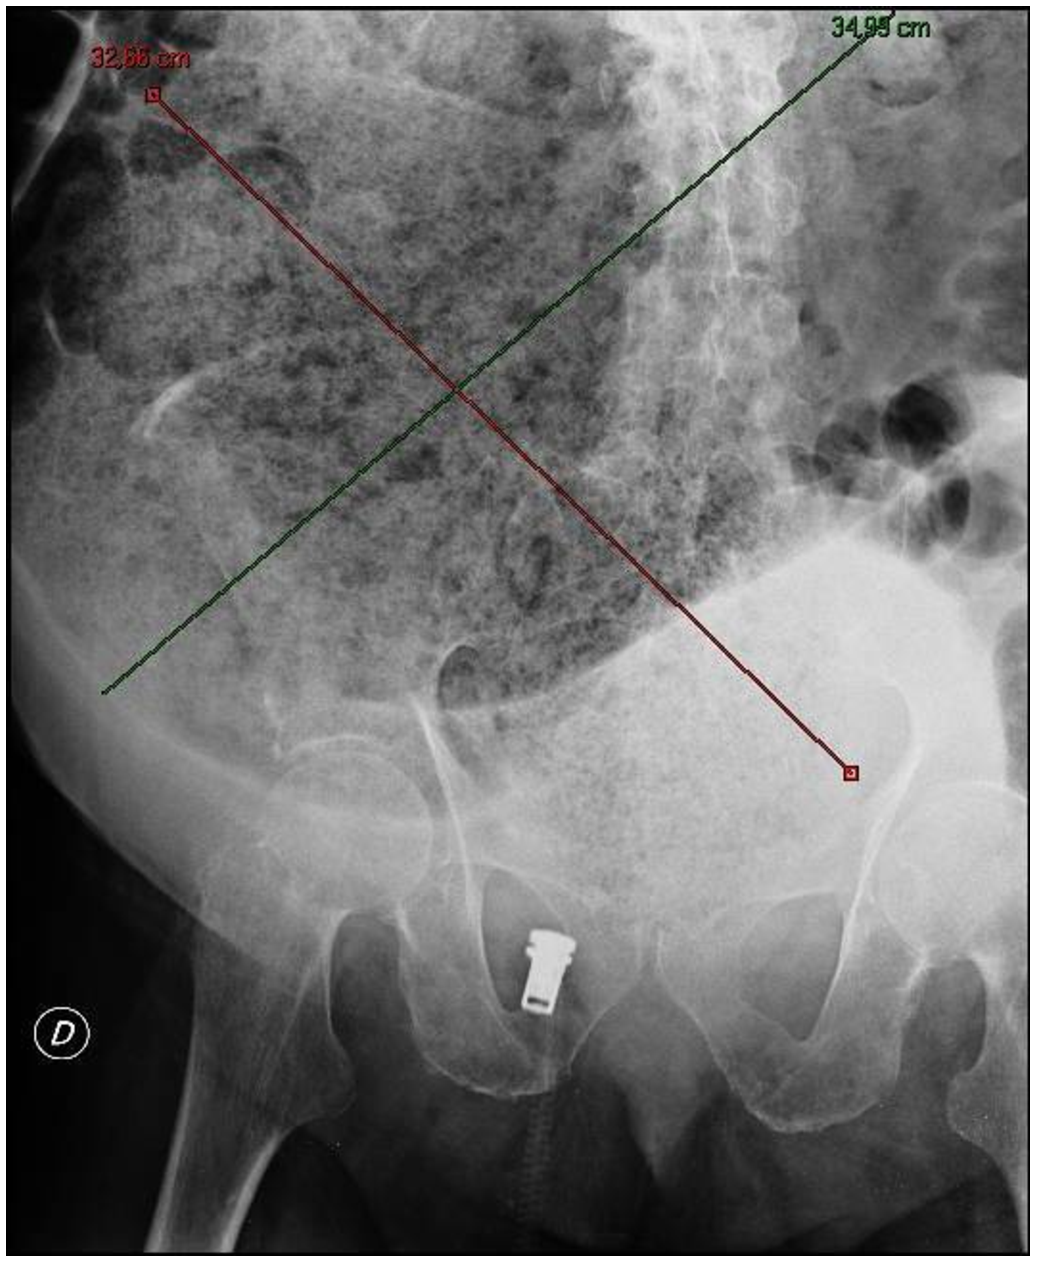

由粪便引起的腹胀过程的X射线图像。